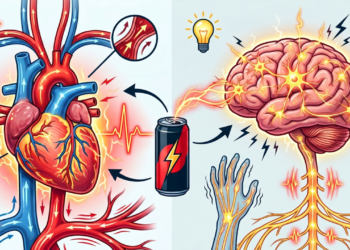

Cortar alimentos ultraprocessados ajuda muito na saúde, mas o benefício real só aparece após alguns dias de adaptação do organismo

Eliminar produtos industrializados da rotina alimentar diária proporciona uma renovação profunda em todos os sistemas do corpo humano ao longo ...